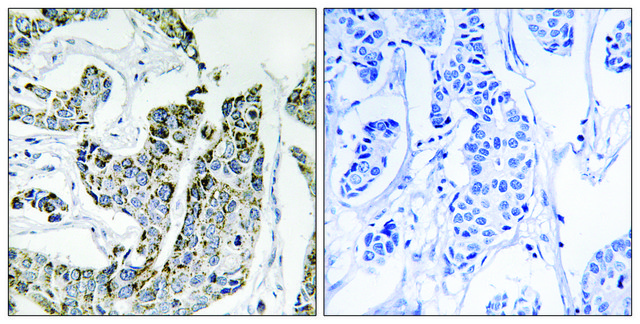

SAB4301289

Anti-phospho-BLK (pTyr501) antibody produced in rabbit

immunohistochemistry: 1:50-1:100

phosphorylation (pTyr501)

Peptide sequence around phosphorylation site of tyrosine 501 (R-Q-Y(p)-E-L) derived from Human BLK.

The antibody detects endogenous levels of BLK only when phosphorylated at tyrosine 501.